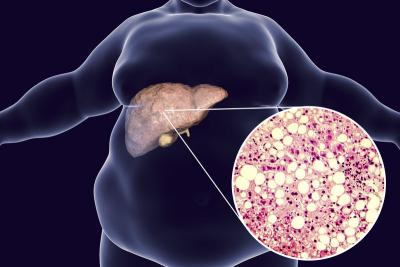

फॅटी लिव्हर-यकृतामध्ये चरबी वाढते तेव्हा फॅटी लिव्हर ज्याला हेपॅटिक स्टेटोसिस देखील म्हणतात. आपल्या यकृतामध्ये जास्त चरबी निर्माण होणे अतिशय गंभीर आहे. प्रोटीनच्या कमतरतेमुळे लिव्हरमधील फॅट वाढू लागते आणि फॅटी लिव्हरची समस्या उद्भवते.